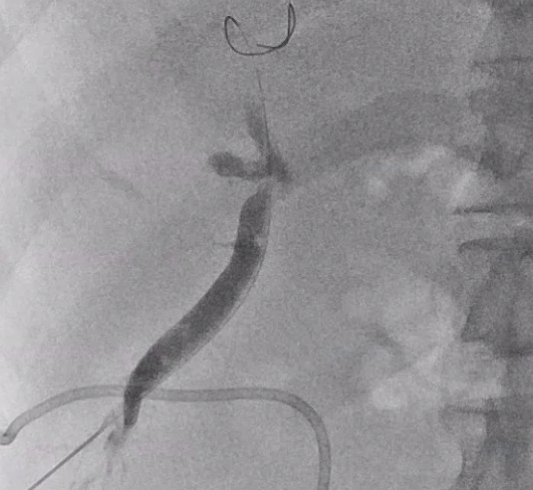

바늘을 통해 와이어를 넣고, 와이어를 따라서 배액관이 들어갑니다.

배액관은 지난 글에서 알려드렸던

이런 돼지 꼬리 모양의 카테터를 넣어 배액관이 잘 빠지지 않게끔 해줍니다. (이름도 돼지 꼬리 입니다.)